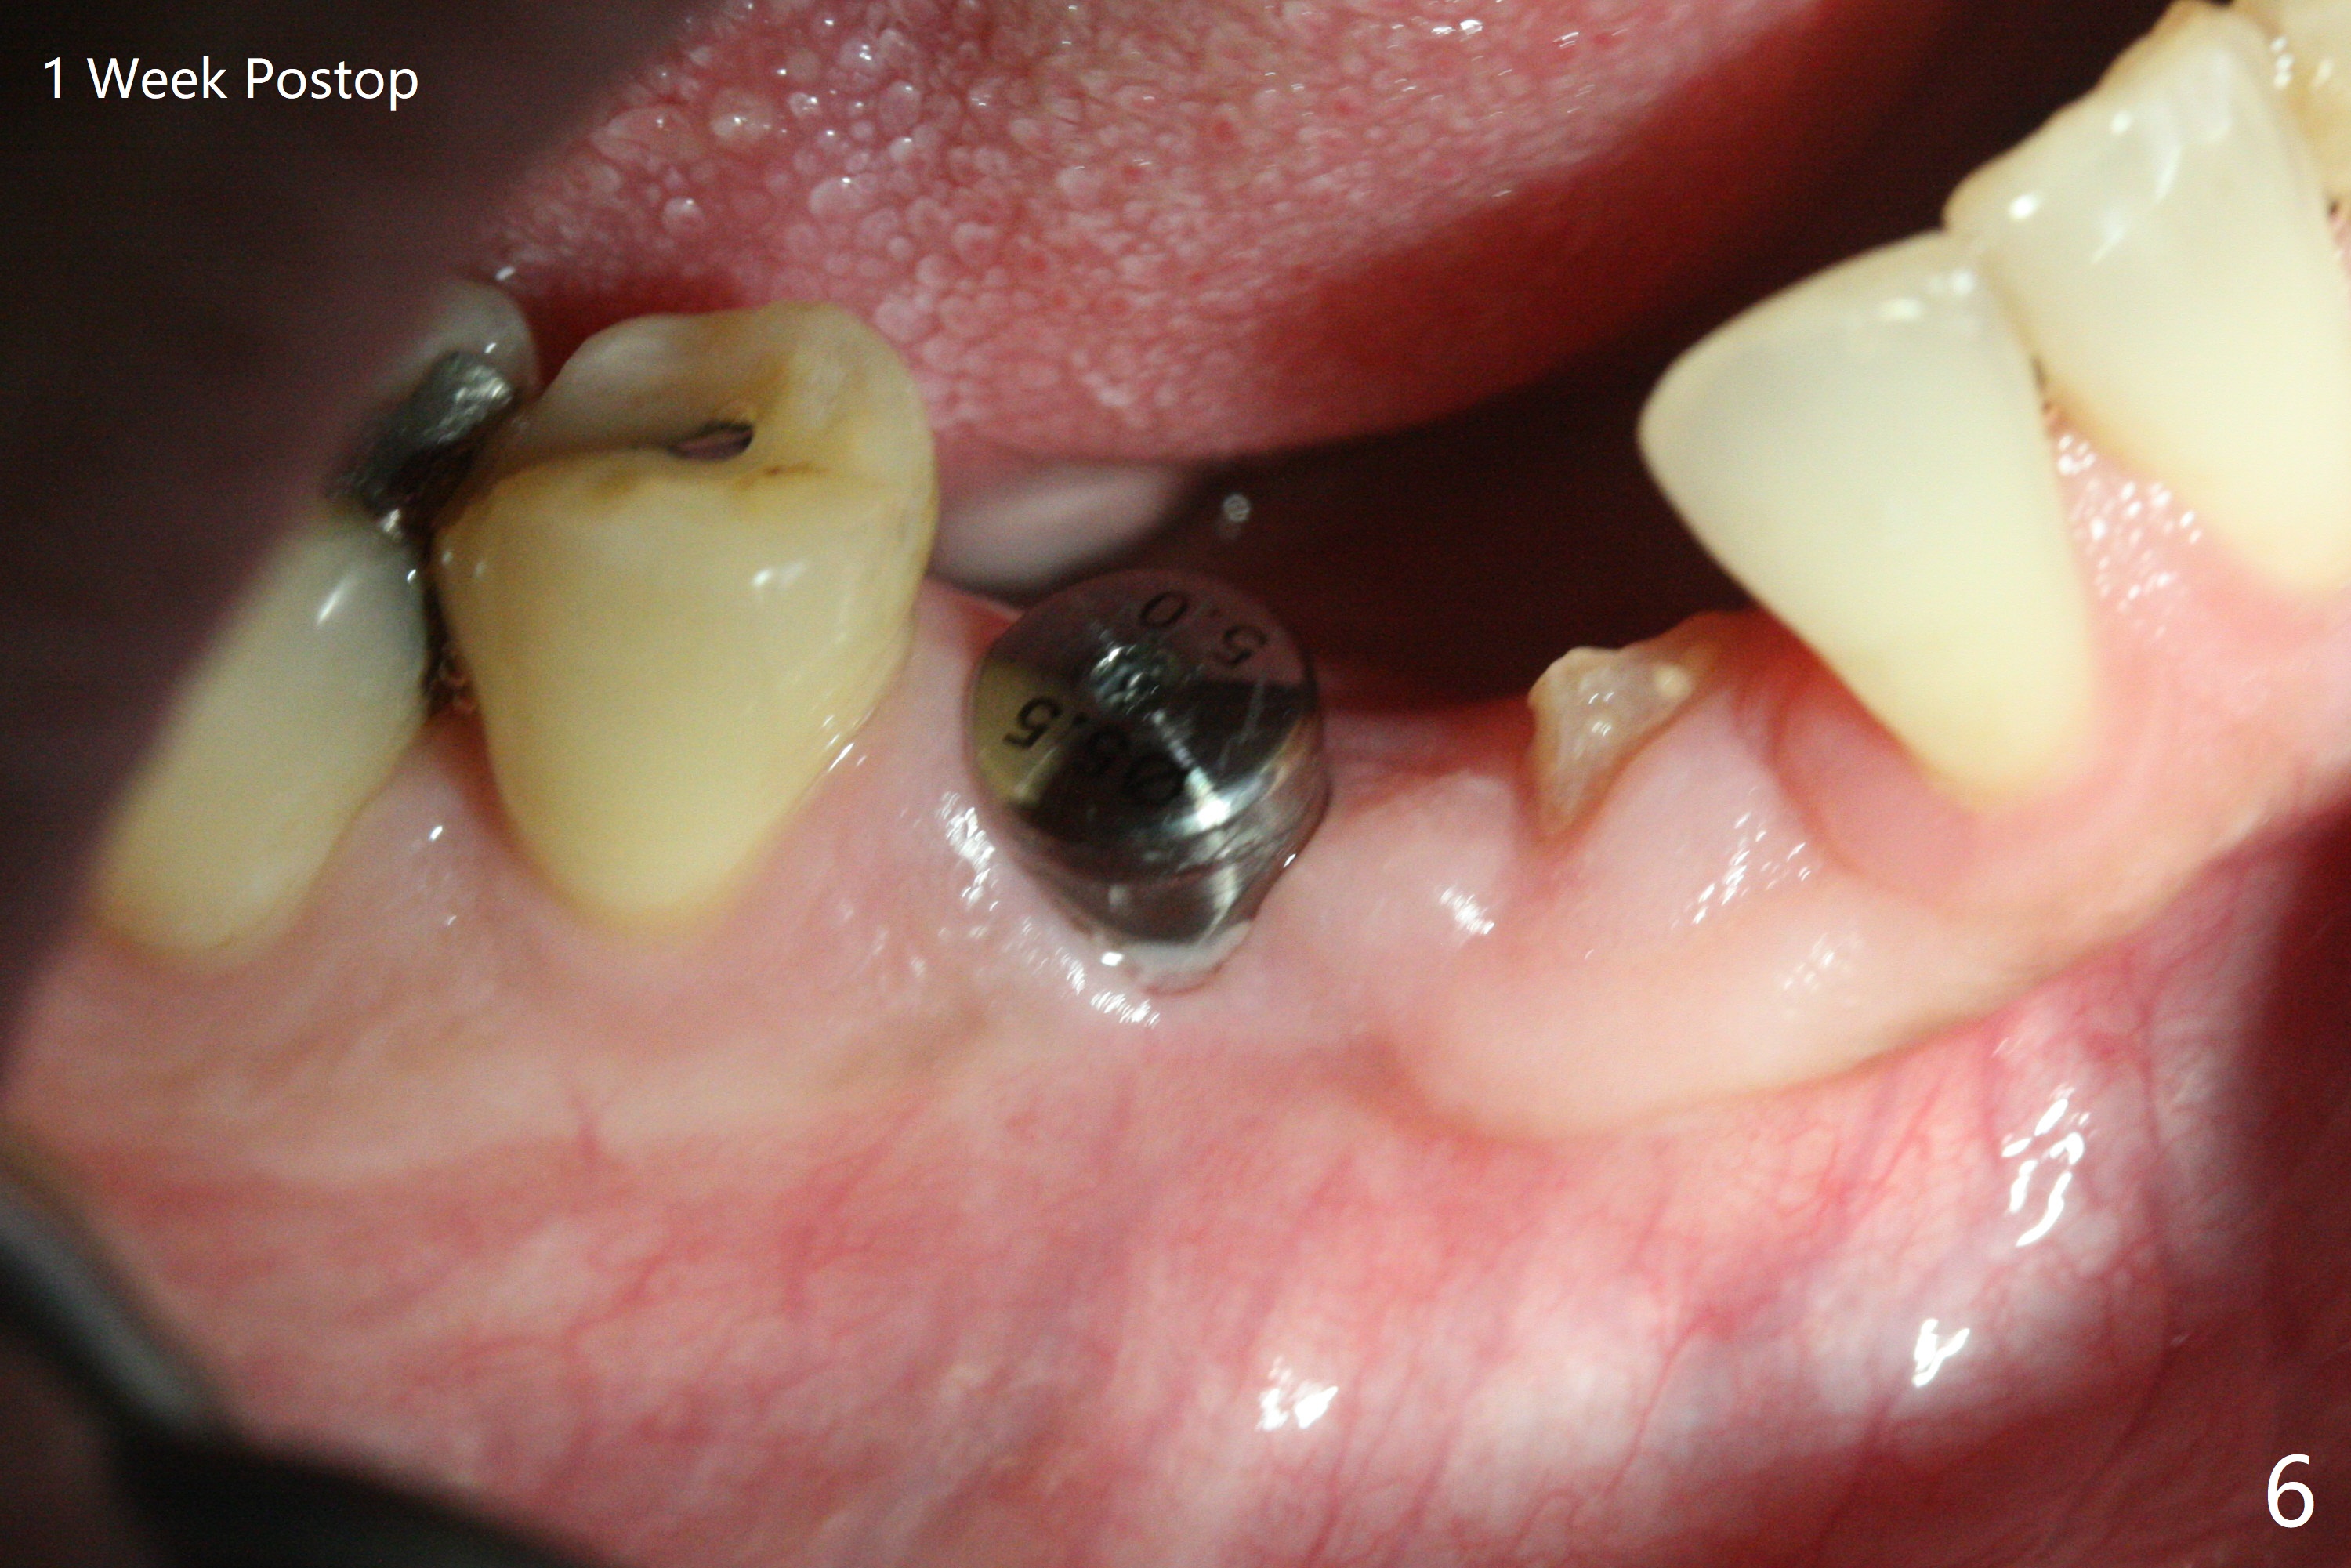

When the surgical guide for #28 is removed, the 4x13 mm implant is found to be superficial and buccal. Part of the buccal mucosa is nonkeratinized. After 1 mm deeper placement of the implant, CT confirms the buccal placement (Fig.1, as compared to design). In fact the guide was doubly checked for fitness prior to osteotomy, but grossly it seemed to be seated properly. The suspicion is related to the trimming at the site of #27 (Fig.2,3 (*), as compared to a mounted model in Fig.4,5 (arrowhead) and the model sent to lab for guide fabrication). The lab agrees to redesign the case. There is a narrow buccal band 1 week postop (Fig.6). The patient is a smoker. The implant was placed buccal (Fig.7, 1 month postop). A new 4x13 mm implant is placed on the top of the 1st line following 3x14.5 mm drill (Fig.8 (35 Ncm)). In fact the implant position is not changed much. Four months post banding (20 ss) and 2 months post 2nd implant placement, the tooth #27 is exposed for bracket; extrusion is initiated (Fig.9). In 3 weeks of retraction, the bracket is supragingival (Fig.10). The canine contacts the distal healing abutment with 2 months of retraction (Fig.11). It seems necessary to initiate lower bracket placement. There is no bone loss 4 months postop (Fig.12). A 4.5x7(4) mm abutment is placed (Fig.13) for a temporary crown as an anchor (Fig.14) to further extrude #27 with continuous inter-arch retraction (to reduce tension upon #26 with severe bone loss (Fig.12)). LR3 extrusion is incomplete, although there is an increase in bone distal to LR2 ~ 10 months of extrusion (Fig.15).